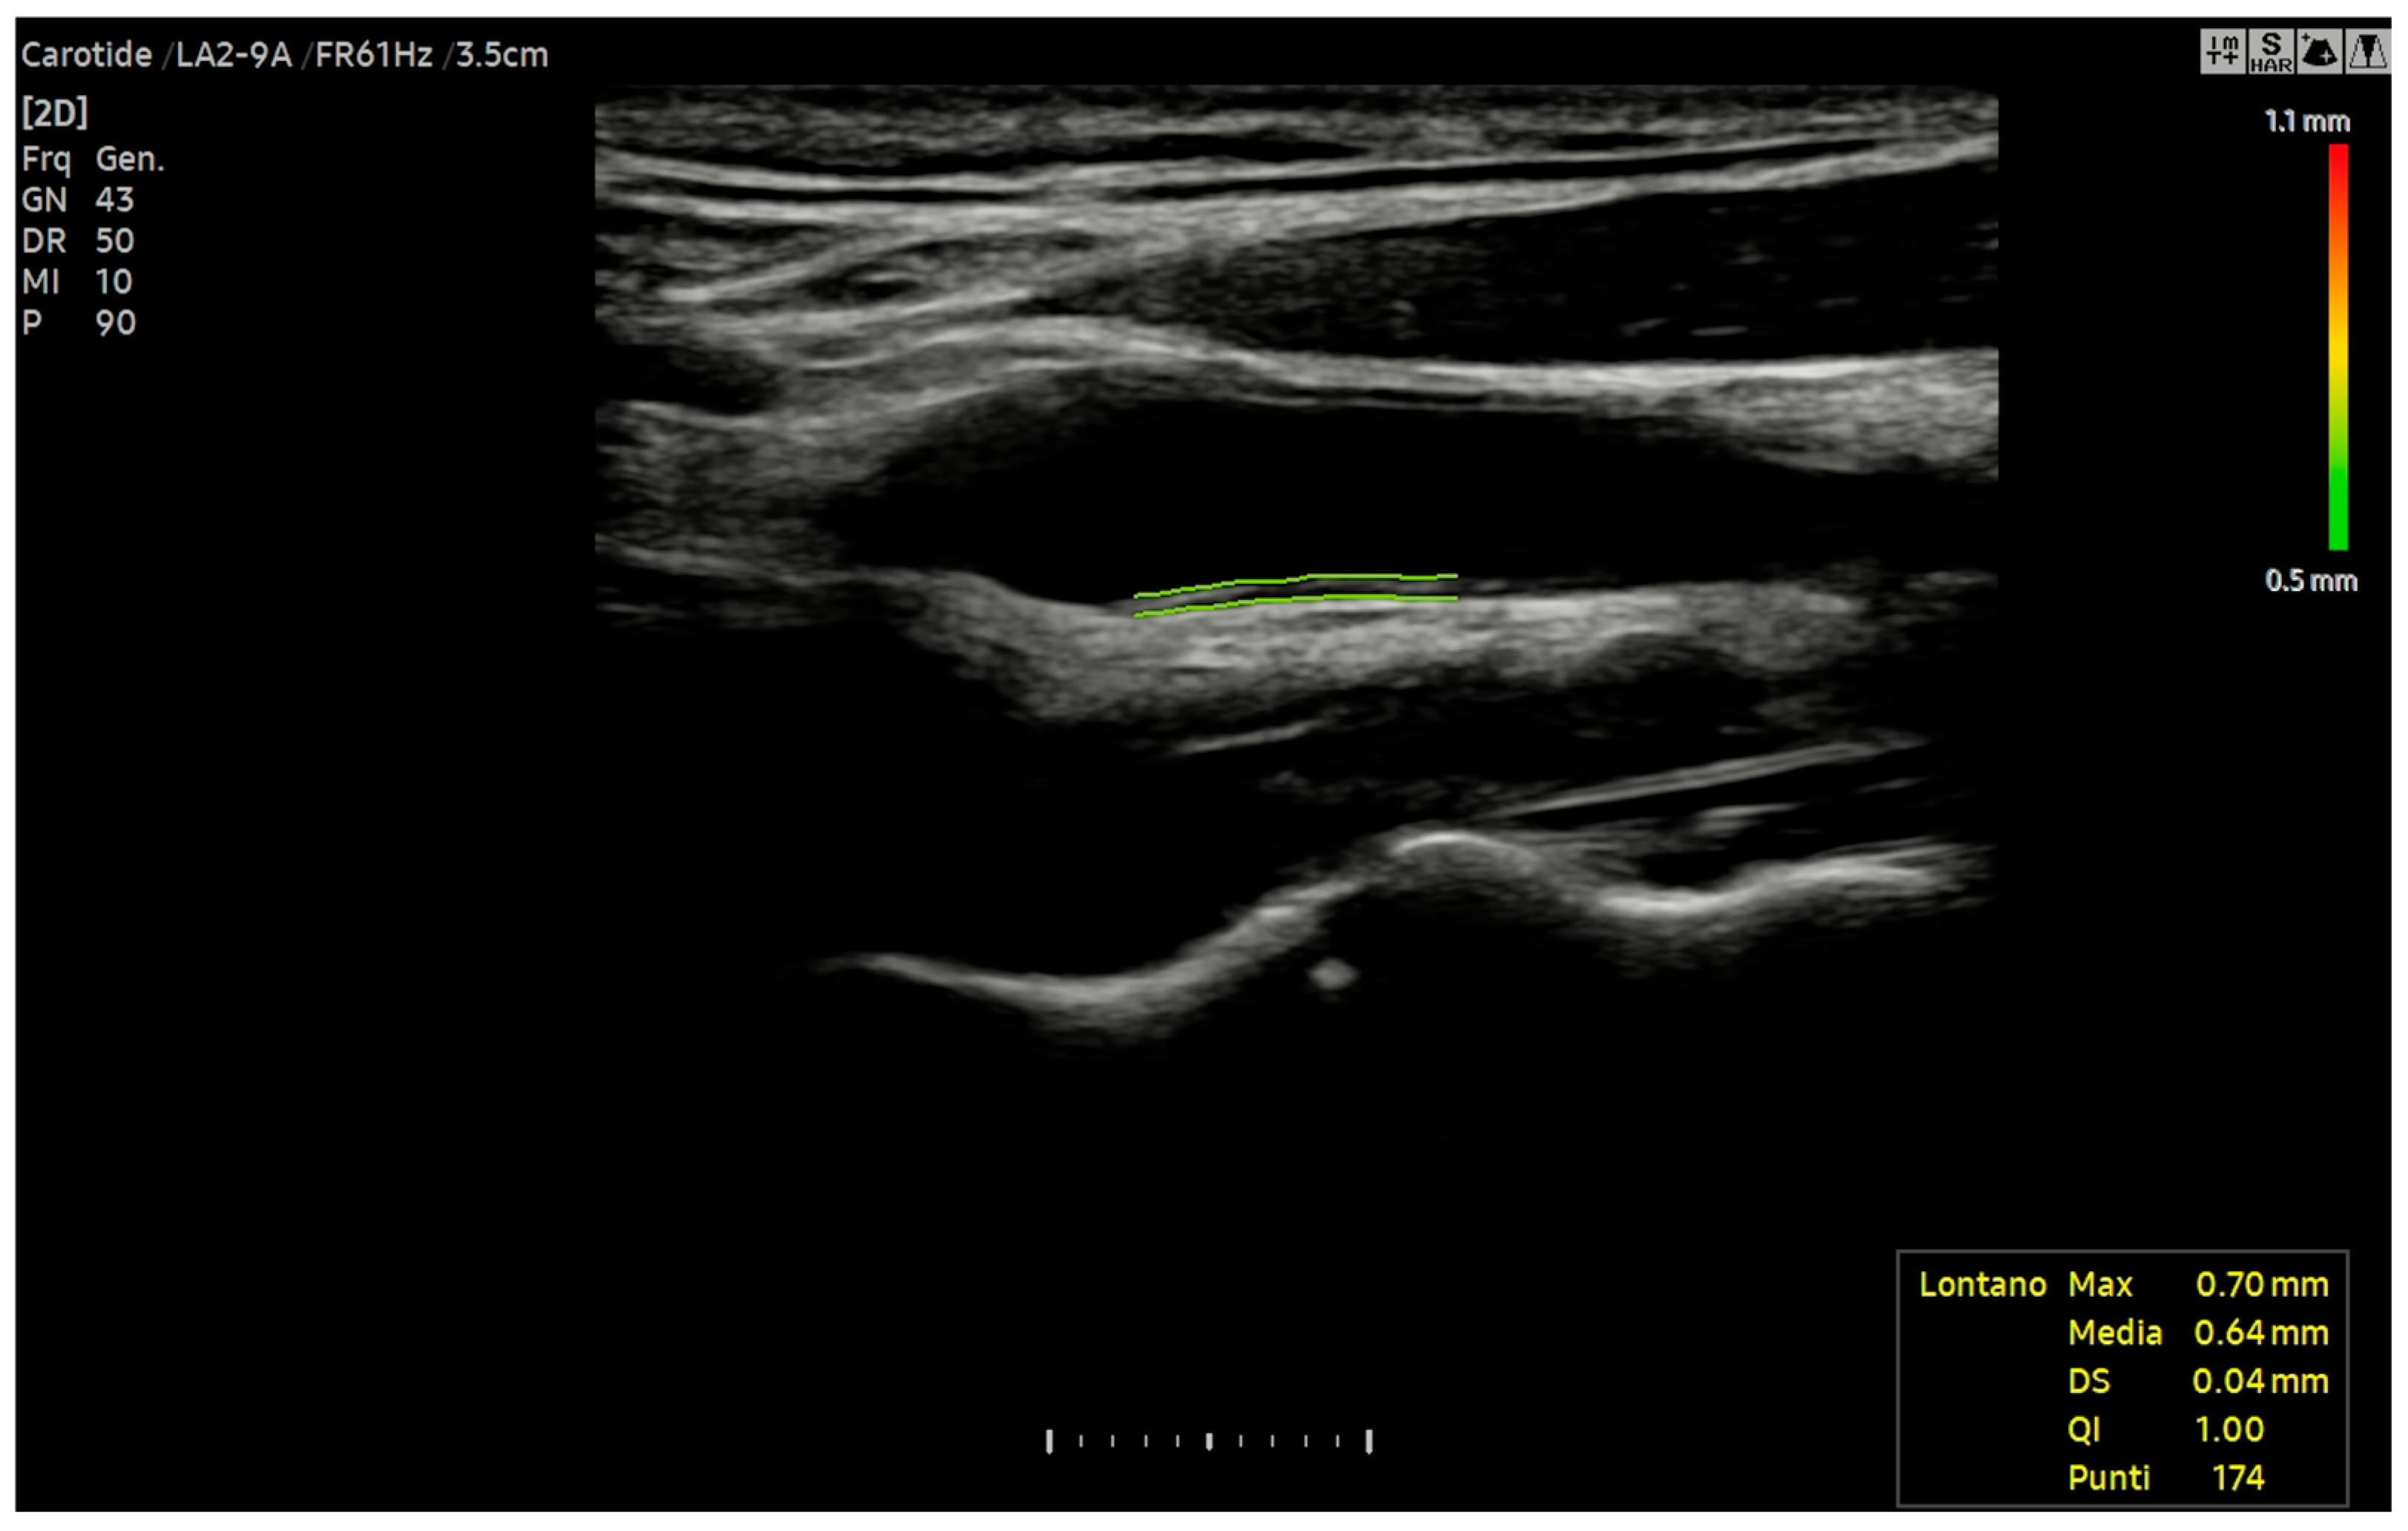

6.4. Carotid Intima-Media Thickness